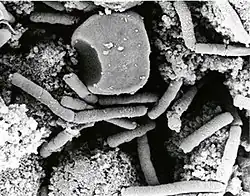

O Bacillus anthracis é um bacilo grande Gram-positivo, com cerca de 8 micrómetros por 3, dispostos aos pares ou individualmente. O B. anthracis, como todos os do seu género, produz endósporos quando encontra situações de adversidade. Os esporos do B.anthracis são centrais, aparecendo a meio do bacilo como uma zona mais clara na técnica Gram.